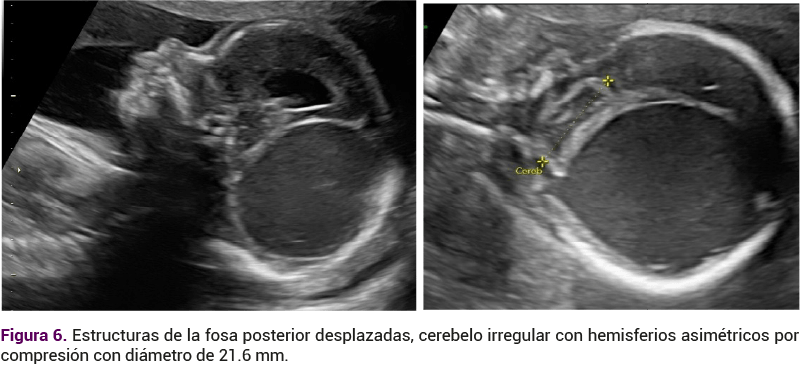

Las estructuras de la fosa posterior se encontraron desplazadas, el cerebelo irregular, con hemisferios asimétricos por compresión, con diámetro de 21.6 mm, con vermis y evidencia de obliteración de la cisterna magna. El cuarto ventrículo estaba comprimido, la cisura de Silvio aplanada (Figura 6), sin alteraciones en las estructuras medio faciales: labio, paladar ni órbitas. La columna vertebral sin alteraciones.

<strong>Figura 6</strong>

Figura 6.